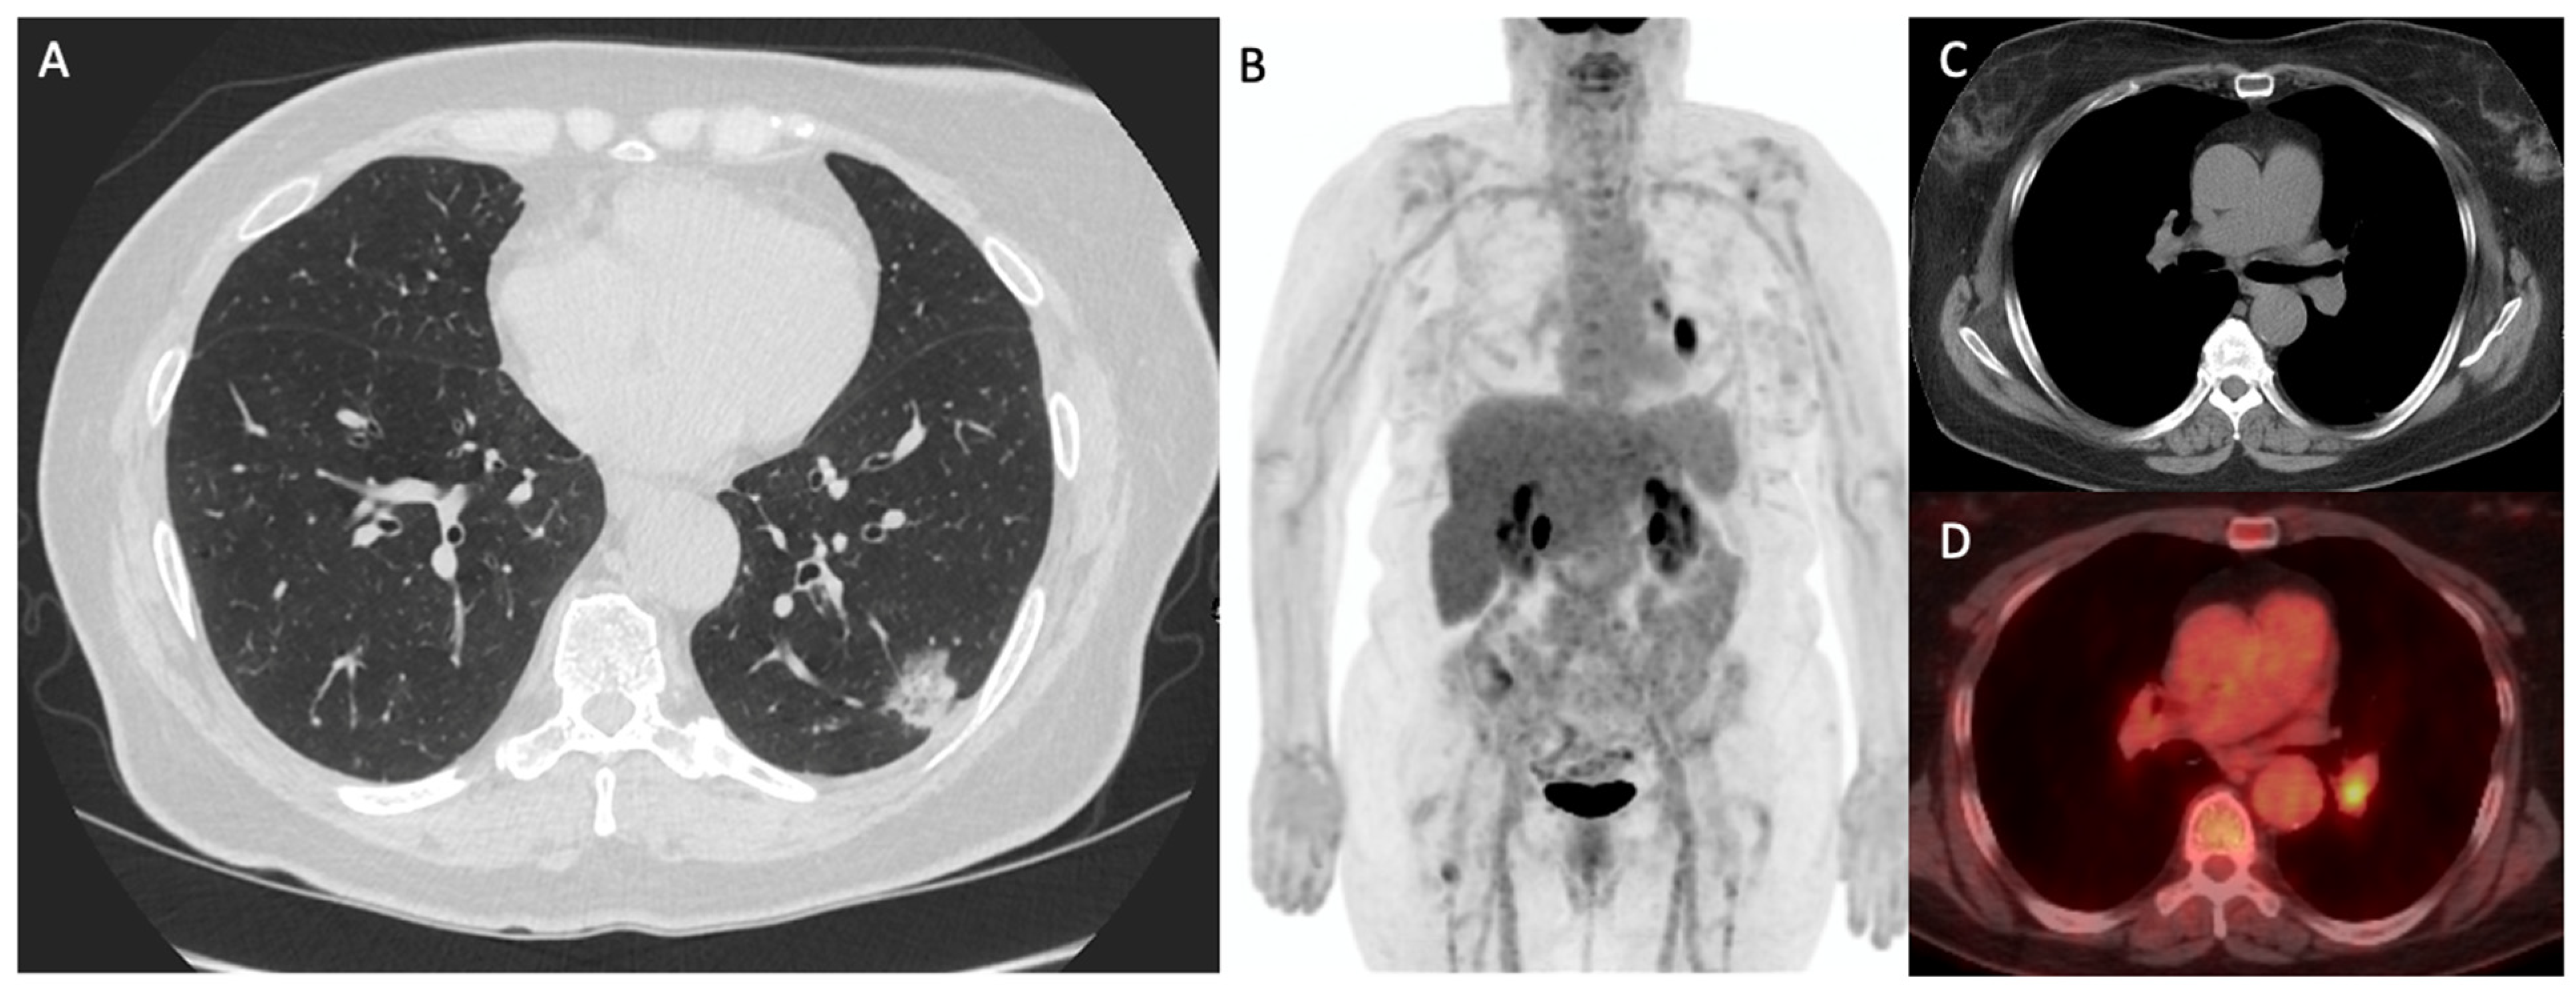

- Szyszko, T.A.; Yip, C.; Szlosarek, P.; Goh, V.; Cook, G.J. The role of new PET tracers for lung cancer. Lung Cancer 2016, 94, 7–14. [Google Scholar] [CrossRef] [PubMed]

- Wang, L.; Tang, G.; Hu, K.; Liu, X.; Zhou, W.; Li, H.; Huang, S.; Han, Y.; Chen, L.; Zhong, J.; et al. Comparison of 68Ga-FAPI and 18F-FDG PET/CT in the Evaluation of Advanced Lung Cancer. Radiology 2022, 303, 191–199. [Google Scholar] [CrossRef] [PubMed]

- Zhou, X.; Wang, S.; Xu, X.; Meng, X.; Zhang, H.; Zhang, A.; Song, Y.; Zhu, H.; Yang, Z.; Li, N. Higher accuracy of [68 Ga]Ga-DOTA-FAPI-04 PET/CT comparing with 2-[18F]FDG PET/CT in clinical staging of NSCLC. Eur. J. Nucl. Med. Mol. Imaging 2022, 49, 2983–2993. [Google Scholar] [CrossRef]

- Gao, S.; Wu, H.; Li, W.; Zhao, S.; Teng, X.; Lu, H.; Hu, X.; Wang, S.; Yu, J.; Yuan, S. A pilot study imaging integrin alphavbeta3 with RGD PET/CT in suspected lung cancer patients. Eur. J. Nucl. Med. Mol. Imaging 2015, 42, 2029–2037. [Google Scholar] [CrossRef] [PubMed]

- Zheng, K.; Liang, N.; Zhang, J.; Lang, L.; Zhang, W.; Li, S.; Zhao, J.; Niu, G.; Li, F.; Zhu, Z.; et al. 68Ga-NOTA-PRGD2 PET/CT for Integrin Imaging in Patients with Lung Cancer. J. Nucl. Med. 2015, 56, 1823–1827. [Google Scholar] [CrossRef] [PubMed]

- Sharma, P.; Singh, S.S.; Gayana, S. Fibroblast Activation Protein Inhibitor PET/CT: A Promising Molecular Imaging Tool. Clin. Nucl. Med. 2021, 46, e141–e150. [Google Scholar] [CrossRef] [PubMed]

- Capaccione, K.M.; Doubrovin, M.; Braumuller, B.; Leibowitz, D.; Bhatt, N.; Momen-Heravi, F.; Molotkov, A.; Kissner, M.; Goldner, K.; Soffing, M.; et al. Evaluating the Combined Anticancer Response of Checkpoint Inhibitor Immunotherapy and FAP-Targeted Molecular Radiotherapy in Murine Models of Melanoma and Lung Cancer. Cancers 2022, 14, 4575. [Google Scholar] [CrossRef] [PubMed]